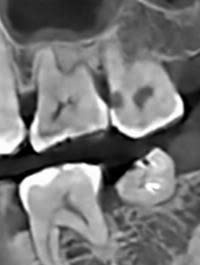

XQuang trước – sau điều trị

Việc quan sát đúng cách có thể giúp loại bỏ sâu răng đầy đủ. Ba điều kiện thiết yếu cần đạt được trong quá trình phẫu thuật để có thể quan sát đúng cách nhằm ngăn ngừa việc loại bỏ men răng/ngà răng không đủ trong quá trình chuẩn bị khoang: (i) trường phẫu thuật thông thoáng, (ii) kiểm soát độ ẩm chặt chẽ và (iii) độ phóng đại phù hợp. Cần có trường phẫu thuật thông thoáng trước khi can thiệp phẫu thuật. Loại bỏ mảng bám, mảnh vụn và cao răng trên/dưới nướu là điều cần thiết. Ngoài ra, để đảm bảo tổn thương có lỗ rỗng và cải thiện khả năng tiếp cận bằng thị giác, việc tách răng bằng cách đặt một dụng cụ tách đàn hồi chỉnh nha trong một tuần để tạo ra một khoảng cách nhỏ ở kẽ răng là rất hữu ích. Kiểm soát độ ẩm thông qua việc sử dụng đê cao su rất hữu ích cho việc phục hồi chất lượng cao. Ngoài ra, sử dụng kính lúp phóng đại giúp giảm tình trạng nhô ra ở rìa răng tới 40%. Tình trạng nhô ra có thể ảnh hưởng đến việc đánh giá kết quả lâm sàng của phục hồi trong các lần tái khám do gây ra sự hiểu sai về lý do thất bại. Thất bại của phục hồi có thể là do nhô ra và rò rỉ thay vì do chính đường hầm. Các phương pháp tiếp cận trái ngược khác để tạo điều kiện loại bỏ sâu răng đầy đủ bao gồm tăng kích thước của đường tiếp cận nhai và áp dụng kiểm tra chụp X quang. Tuy nhiên, việc tăng kích thước của quá trình chuẩn bị đường hầm sẽ làm giảm khả năng chống gãy của răng. Một nghiên cứu đã báo cáo rằng ngay cả việc kiểm tra chụp X quang tại chỗ trong quá trình chuẩn bị đường hầm cũng không thể làm tăng hiệu quả của việc loại bỏ sâu răng. Người ta cho rằng không nên coi chụp X-quang là công cụ chẩn đoán phù hợp để xác định sâu răng trong quá trình chuẩn bị đường hầm.